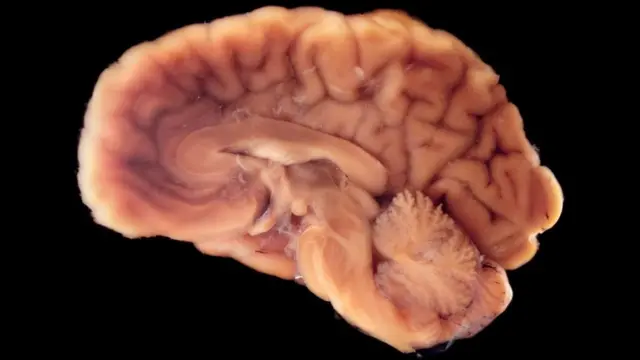

Para calificar como cadáver de corazón latiente, todo el cerebro debe estar muerto.

Esto incluye el "tronco cerebral", la masa primitiva en forma de tubo en la parte inferior del cerebro que controla funciones corporales críticas, como la respiración. Pero -y esto es desconcertante- nuestros otros órganos no están tan preocupados por la muerte de su "cuartel general" como se podría pensar.

Fuente de la imagen, Science Photo Library